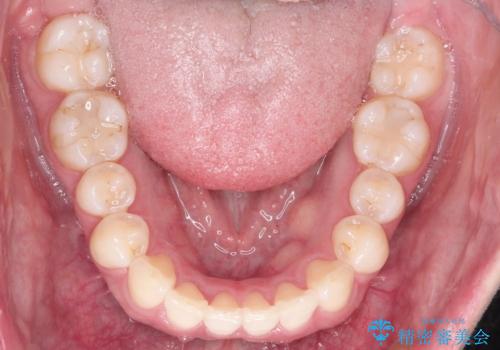

初診時の歯並びの状態としては、下顎前歯に及ぶの中等度のがたつき(叢生)があり、前歯が深く噛みこんでいる状態でした。

抜歯は行わず歯列弓の拡大やディスキング(歯と歯の間の隙間を作る処置)を行い叢生を改善しました。

見た目、嚙み合わせ及び、治療期間や施術内容に大変ご満足いただきました。